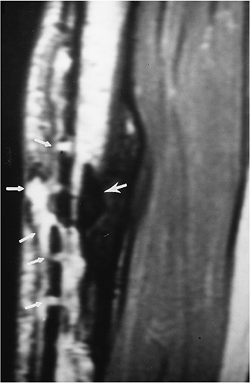

![]() |

FIGURE 11-6

Old tibial fracture with plate and screw fixation removed because of infection. Sagittal T2-weighted image demonstrates a sequestrum (arrow) with fluid exiting the old pin tracts (small arrows) and a long abscess cavity anteriorly. |